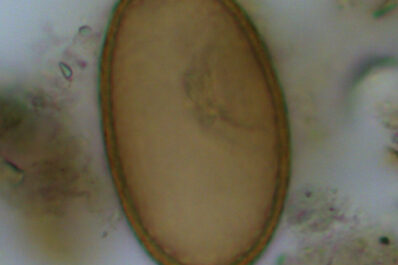

A new analysis of ancient faeces found at the site of a prehistoric village near Stonehenge has uncovered evidence of...